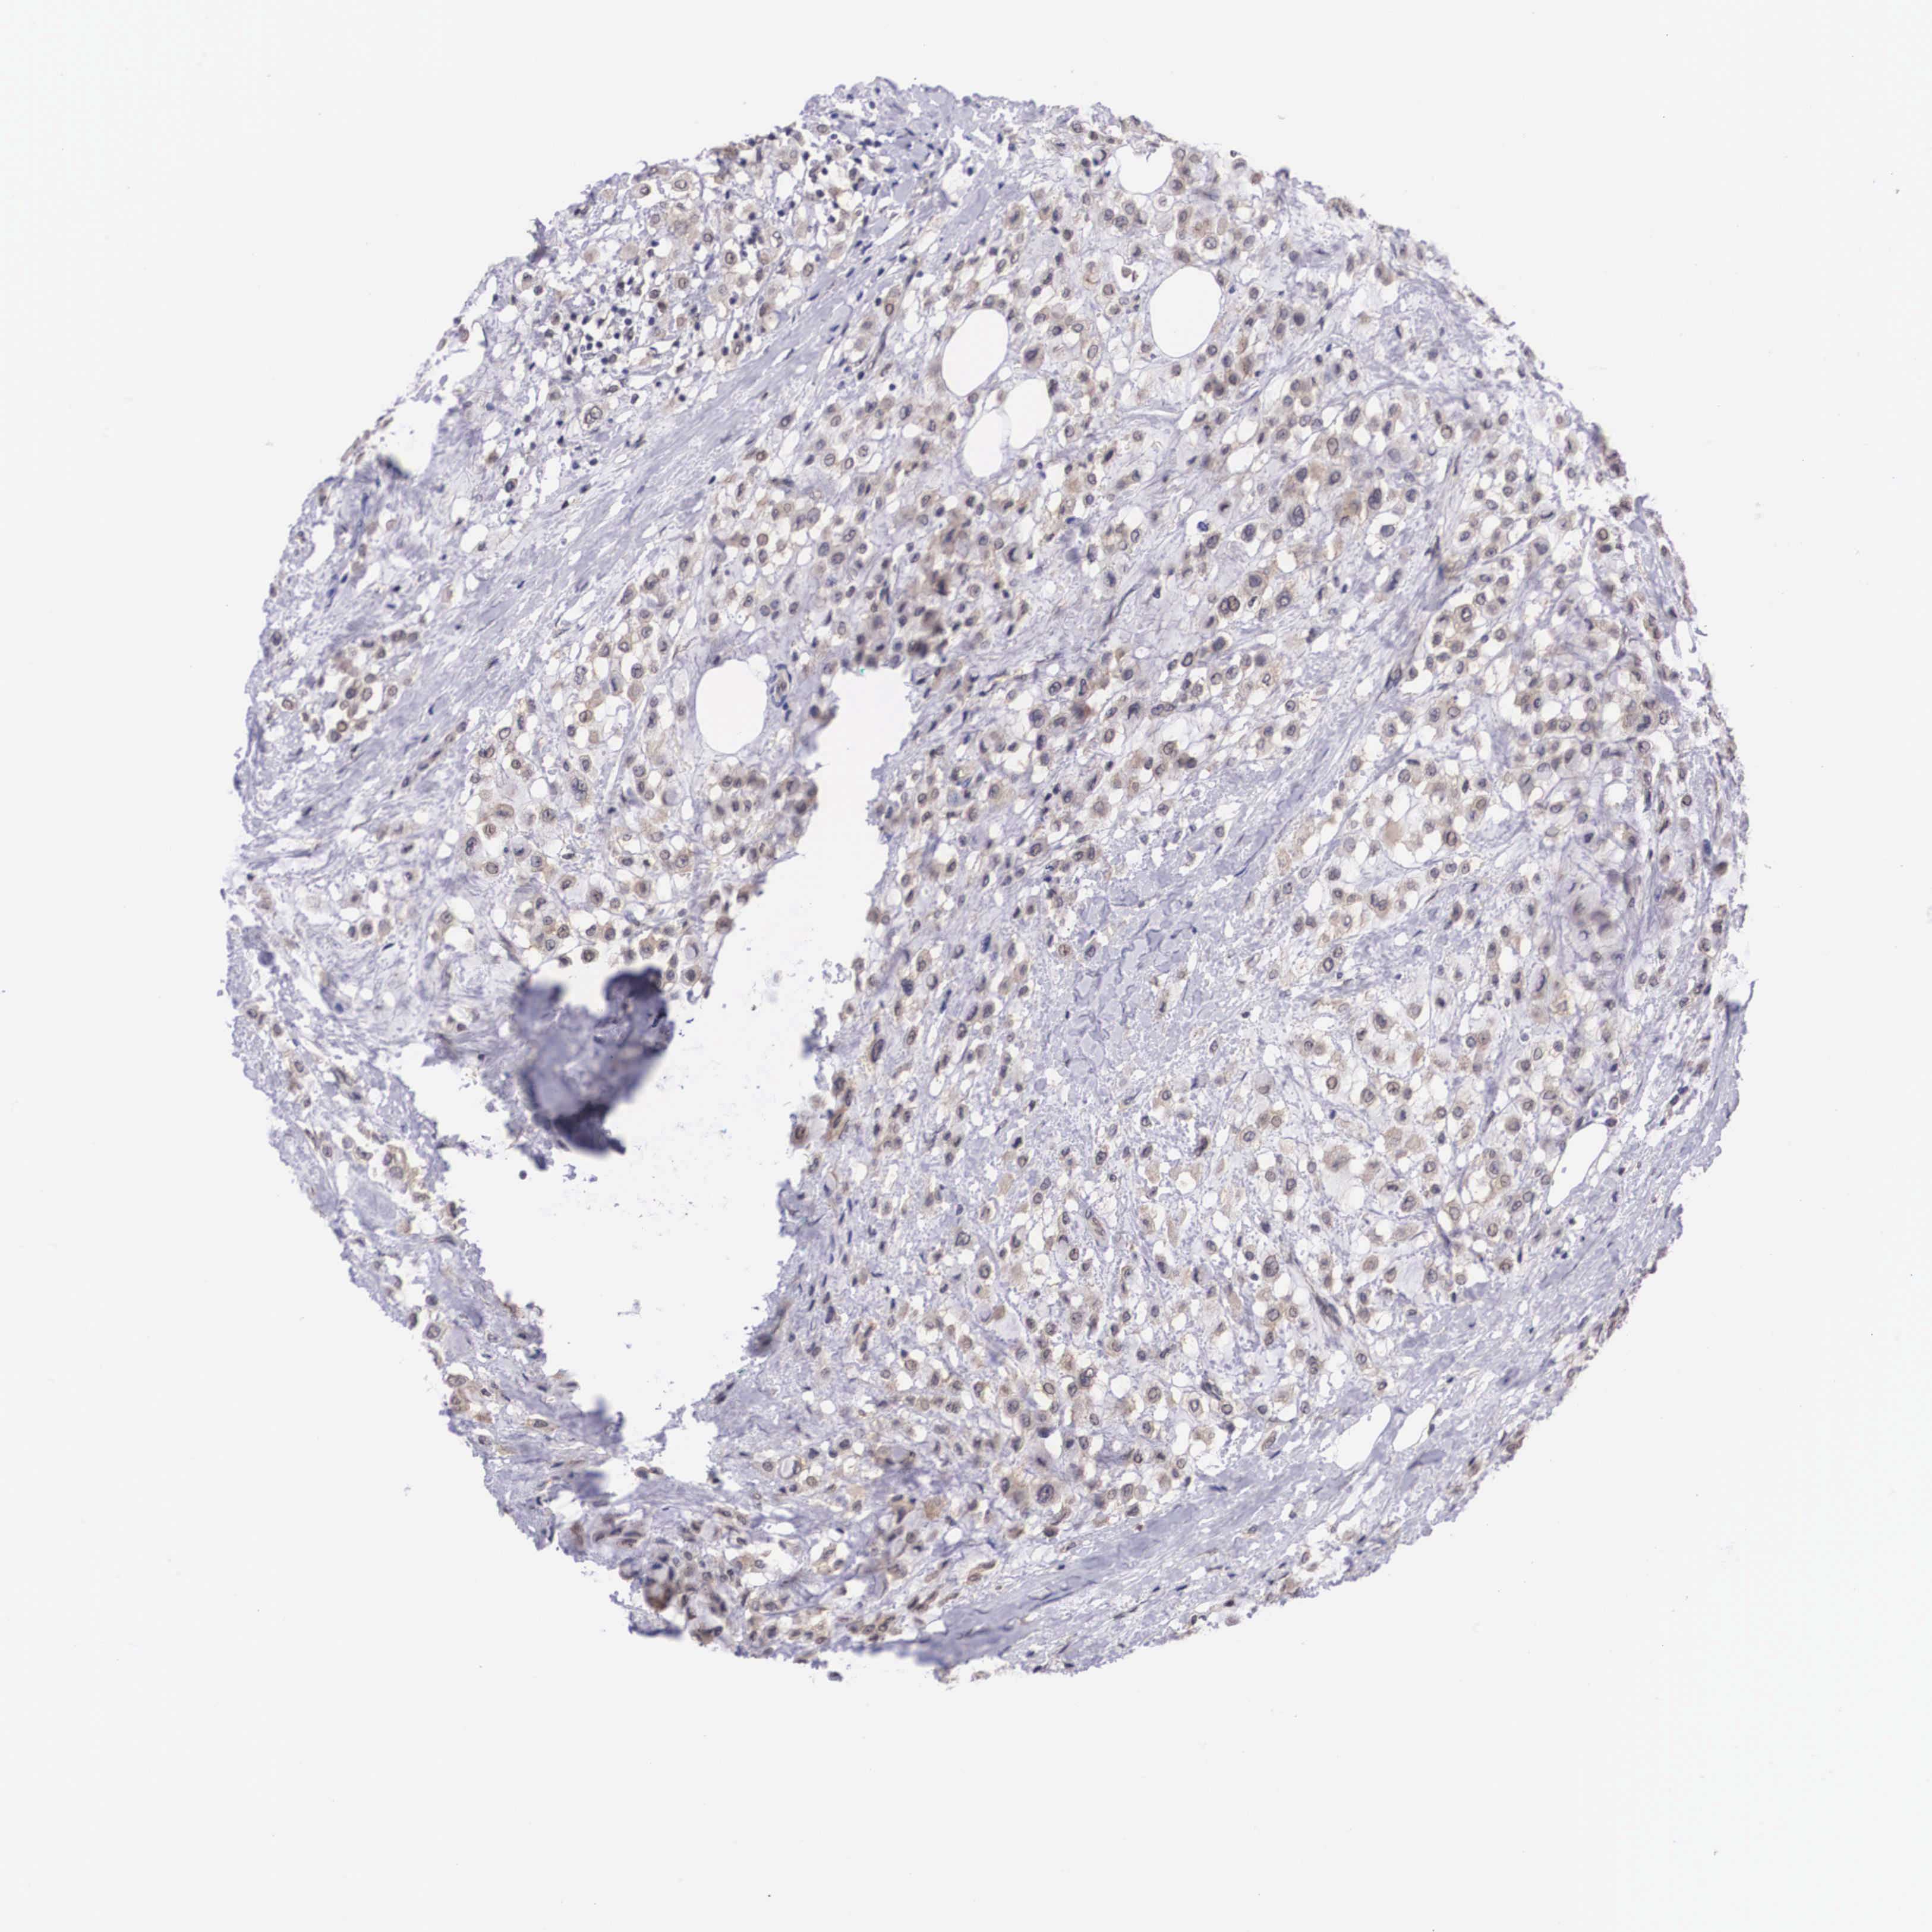

CANCER BREAST CANCER Show tissue menu

Breast cancer